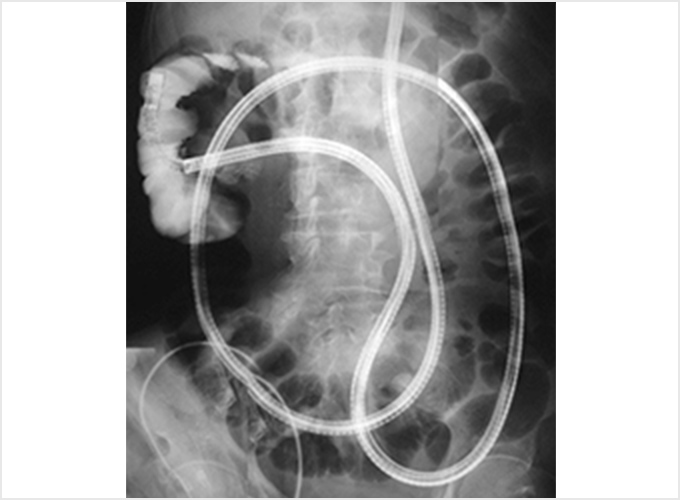

ダブルバルーン内視鏡

ダブルバルーン内視鏡は、小腸の出血性病変を疑う場合や小腸の通過障害、クローン病などの病気が疑われる場合などに適応となります。 ダブルバルーン内視鏡とは、長さ2mの長いスコープとバルーンの付いたオーバーチューブを組み合わせたものです。 小腸内で2つのバルーンを交互に膨らませて固定し、腸管をたたみ込んで内視鏡を進めることで、内視鏡検査が難しかった小腸全体の内視鏡精密検査・治療を可能にしました。

バルーン内視鏡は、X線透視で適宜位置を確認しながら進めます。経口的にも経肛門的にも挿入することが可能で、両方向からの挿入を組み合わせることにより小腸すべてを観察することもできます。観察するだけでなく、出血病変に対して止血したり、ポリープを切除したり、狭いところを広げたりすることもできます。

内視鏡的逆行性胆管膵管造影:ERCP(Endoscopic retrograde cholangiopancreatography)

内視鏡的逆行性胆管膵管造影(ERCP)は、十二指腸までスコープを進め、内視鏡の先端から造影カテーテルという細いチューブを膵管や胆管に挿入し、造影剤を直接注入してX線撮影を行います。 X線撮影だけではなく、管腔内超音波内視鏡(IDUS)を用いて胆管内を観察したり、顕微鏡で調べる組織を採取することも可能です。

また、内視鏡の先端から出したバスケット把持鉗子やバルーン付きカテーテルを用いて、胆管結石を砕いたり取り除いたり(採石)する治療や、腫瘍などで閉塞(狭窄)した胆管にステントを挿入し、胆汁の流れを良くする治療なども行っています。